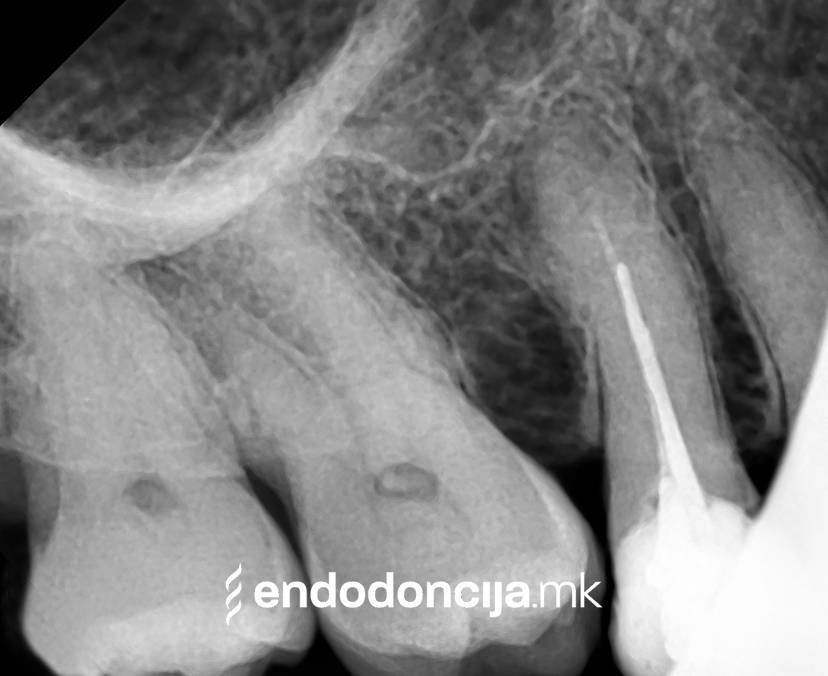

Σε περίπτωση ανανέωσης της θεραπείας του ριζικού καναλιού (αναθεώρηση) παλιά γεμίσματα ρίζας που δεν ήταν επιτυχημένα και ως εκ τούτου ήταν η αιτία φλεγμονών και πόνου, μπορούν να αφαιρεθούν και να ανανεωθούν εξειδικευμένα. Αυτή η θεραπεία εξαλείφει τις φλεγμονές στην περιοχή της ρίζας και καθίσταται δυνατή η πλήρης ανάρρωση.

Κατά τη διάρκεια προηγούμενων θεραπειών, το δόντι μπορεί όχι μόνο να έχει αποδυναμωθεί από τη μηχανική επεξεργασία του ριζικού σωλήνα αλλά και από τη στερέωση και την αγκύρωση ενός ρίζα. Όταν αναθεωρείται η επεξεργασία ενός ριζικού καναλιού, αυτοί οι πείροι πρέπει να αφαιρούνται όσο το δυνατόν πιο προσεκτικά για να διατηρούν σημαντική ουσία των δοντιών.

Με τη σωστή θεραπεία, όχι μόνο οι οξείες φλεγμονές αλλά και οι χρόνιες μπορούν επίσης να αντιμετωπιστούν με επιτυχία. Αυτά μπορεί να προκαλέσουν πόνο ή μερικές φορές ακόμη και εντελώς χωρίς συμπτώματα. Η έγκαιρη ανίχνευση και εξάλειψη τέτοιων φλεγμονών είναι ζωτικής σημασίας για τη μακροχρόνια συντήρηση των δοντιών.